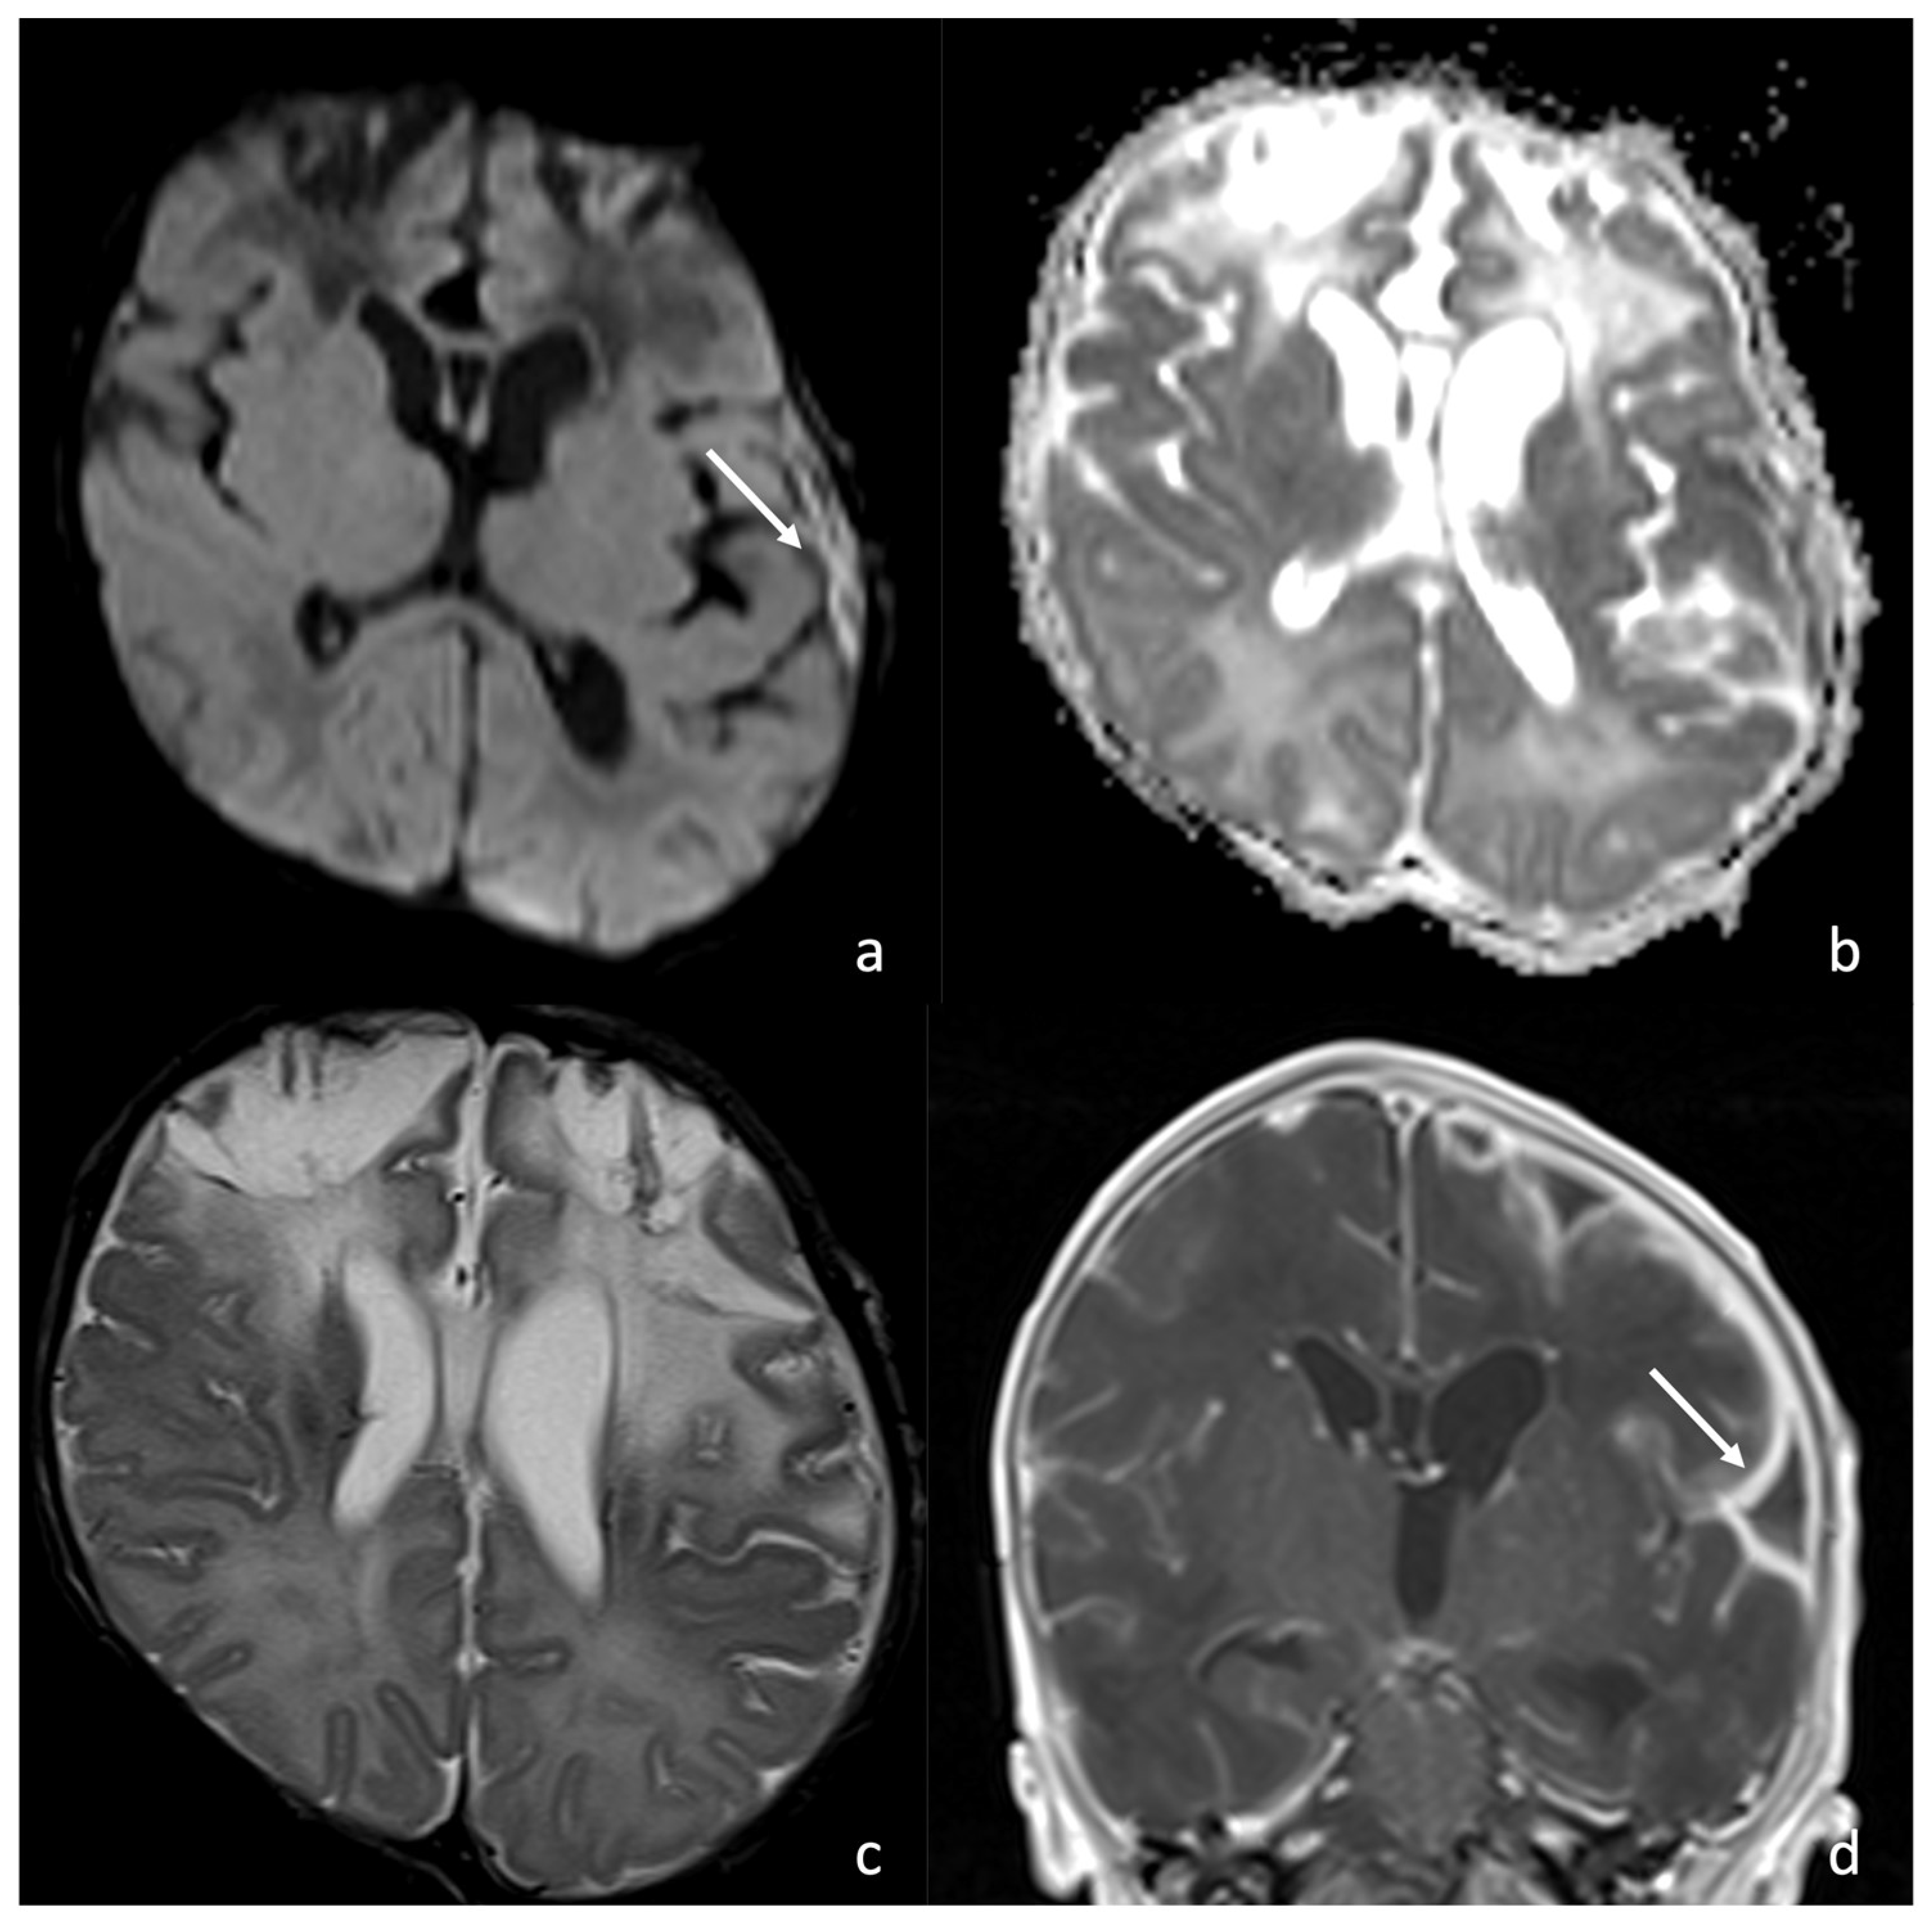

Figure 3.

A 9-day-old boy affected by meningitis caused by Listeria Monocytogenes with ventriculitis. There are hypointense in T2 (arrow in (a), axial T2WI) and hyperintense detritus in T1 (arrow in (b), axial T1-weighted images); a slight contrast enhancement of ventricle wall is visible in (d), axial post- contrast T1 WI, especially if compared with (c) axial pre-contrast T1 WI. There is also a ventriculomegaly visible on both MRI ((e), coronal T2WI; (f), sagittal T1 WI) and US ((g), coronal plane and (h), parasagittal plane). In (f,h), there are also visible hyperintense ((f), arrow) and hyperechogenic detritus ((h), arrow).